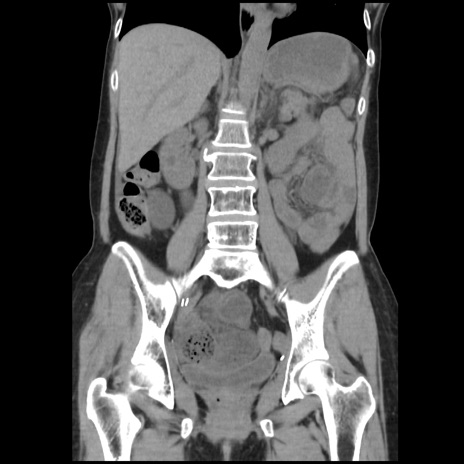

症例32(冠状断像)

【症例】40歳代 女性

【主訴】上腹部痛、嘔気・嘔吐

【現病歴】約9時間前頃から急に上腹部痛、嘔気、嘔吐が出現。改善しないため救急要請。

【既往歴】子宮頚癌(広汎子宮全摘術、放射線療法)、腸閉塞

【身体所見】腹部:平坦、軟、腸雑音亢進、上腹部を中心に腹部全体に圧痛あり。

【データ】WBC 8400、CRP 0.03